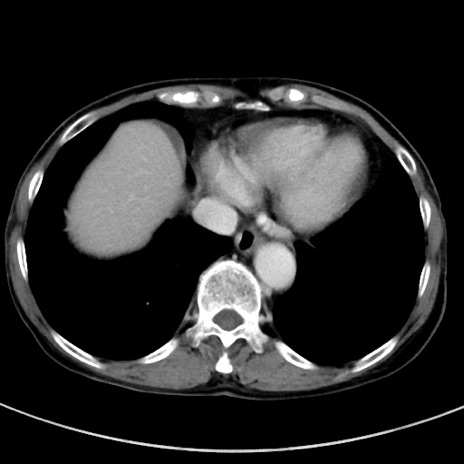

症例23(横断像)

【症例】70歳代女性

【主訴】下腹部痛・嘔吐

【現病歴】2日前より腹痛あり。昨日嘔吐あり。症状改善しないため来院。

【既往歴】胃GISTに対して胃部分切除後。

【身体所見】BT 37.1℃、BP 128/77mmHg、腹部:平坦・軟、下腹部に圧痛あり。

【データ】WBC 10200、CRP 0.31